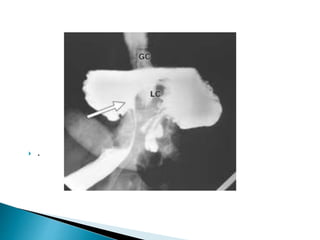

Ba contrast enema

contrast-filled rectum

illustrates the "bird's beak"

sign (white arrow),

corresponding to the

luminal narrowing at the

site of sigmoid obstruction.

This is the characteristic

presentation of a sigmoid

volvulus